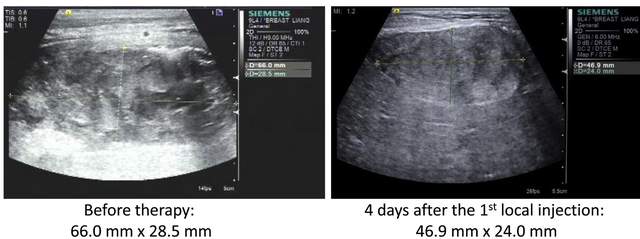

广州某医院曾应用CAR-NK细胞治疗结直肠癌患者,其中1例患者CAR-NK细胞治疗4天后,肝脏区域肿瘤大小由66.0mm×28.5mm缩小至46.9mm×24.0mm。